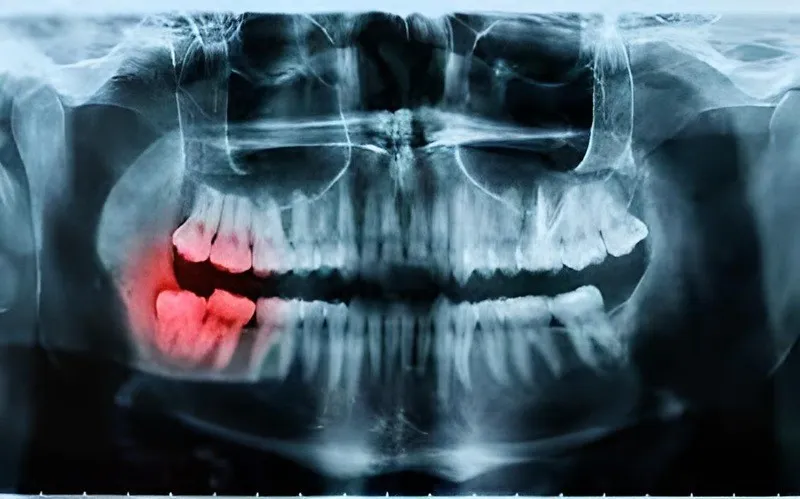

Trước khi tham khảo dịch vụ chụp X-quang răng ở Hải Phòng, hãy cùng tìm hiểu qua về phương pháp y khoa này. Chụp X-quang răng là kỹ thuật chẩn đoán hình ảnh sử dụng tia X để ghi lại cấu trúc bên trong khoang miệng, bao gồm răng, xương hàm, chân răng, tủy và các mô mềm xung quanh. Phương pháp này cung cấp hình ảnh chi tiết giúp các bác sĩ nha khoa đánh giá chính xác tình trạng răng miệng của bệnh nhân, hỗ trợ trong việc chẩn đoán và điều trị hiệu quả.

- Phát hiện các vấn đề như sâu răng, viêm tủy, hoặc nhiễm trùng mà mắt thường khó nhìn thấy. Đồng thời, giúp nhận biết tổn thương ở xương hàm như viêm nhiễm, u, nang,…

- Hình ảnh X-quang hiển thị rõ các vùng nằm sâu dưới nướu, như chân răng hoặc vùng xung quanh răng bị tổn thương. Điều này rất quan trọng trong việc đưa ra chẩn đoán chính xác để phục vụ các công đoạn khám bệnh khác.